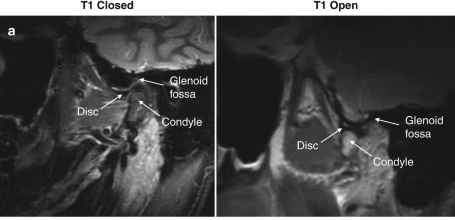

6

A